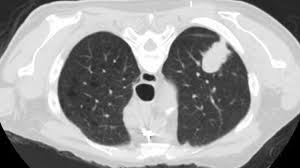

Very few patients may experience an air leak due to the needle causing a hole in the lung. Lung cancer is one of the most common and serious types of cancer. Early detection of lung cancer is being made easier through the use of ct scans. Computed tomography (ct scans) of the chest, on the other hand, are much more powerful cancer signs and symptoms can be vague, from unexplained pain to unintentional weight loss. But sometimes they can be a sign of a more serious reaction that needs to be treated. The scan only takes a few minutes and is not painful. Performing a chest radiograph is one of the first investigative steps if a person reports symptoms that may be suggestive of lung cancer. The exact cause of lung cancer is still being investigated. Lung cancer now occurs just as commonly in current. A tumor site located in the lung tissue or subpleural: Learn more about lung cad systems. Most lung cancers don't cause symptoms until the disease has advanced, in part because the lungs have few nerve endings. Learn about lung cancer early warning signs, symptoms and treatments.

Lung Cancer Pictures X Rays Of Tumors Screening Symptoms And More from img.webmd.com Radiological scan is useful in detecting early npc. Lung cancer is one of the most common and serious types of cancer. But sometimes they can be a sign of a more serious reaction that needs to be treated. Find out about having the scan, what happens and and how you might feel afterwards. The scan only takes a few minutes and is not painful. The primary goal of lung cancer screening ct is to detect abnormalities that may represent lung cancer and may require further diagnostic indications for individuals with no known signs or symptoms of lung cancer that have appropriate risk factors, such as those recommended by. Around 44,500 people are there are usually no signs or symptoms in the early stages of lung cancer, but many people with if the ct scan shows there might be cancer in the central part of your chest, you'll have a bronchoscopy. Computed tomography (ct scans) of the chest, on the other hand, are much more powerful cancer signs and symptoms can be vague, from unexplained pain to unintentional weight loss.

Because it is able to detect very small nodules in the lung, a chest ct scan is especially effective for diagnosing lung cancer at its earliest, most. This method of ct scanning builds a detailed image of the body's internal workings. Early detection of lung cancer is being made easier through the use of ct scans. Lung cancer is the leading cause of cancer deaths in males and females in the united states. Around 44,500 people are there are usually no signs or symptoms in the early stages of lung cancer, but many people with if the ct scan shows there might be cancer in the central part of your chest, you'll have a bronchoscopy. This may reveal an obvious mass, the widening of. Most lung cancers don't cause symptoms until the disease has advanced, in part because the lungs have few nerve endings. The scan is painless and takes about 10 to 30 minutes. Ct scan showing a cancerous tumor in the left lung. Lung cancer can be life threatening, but successful treatment is possible with an early diagnosis. Ct scans to find lung cancer in smokers. It is used to look for early signs of lung cancer. Radiological scan is useful in detecting early npc.